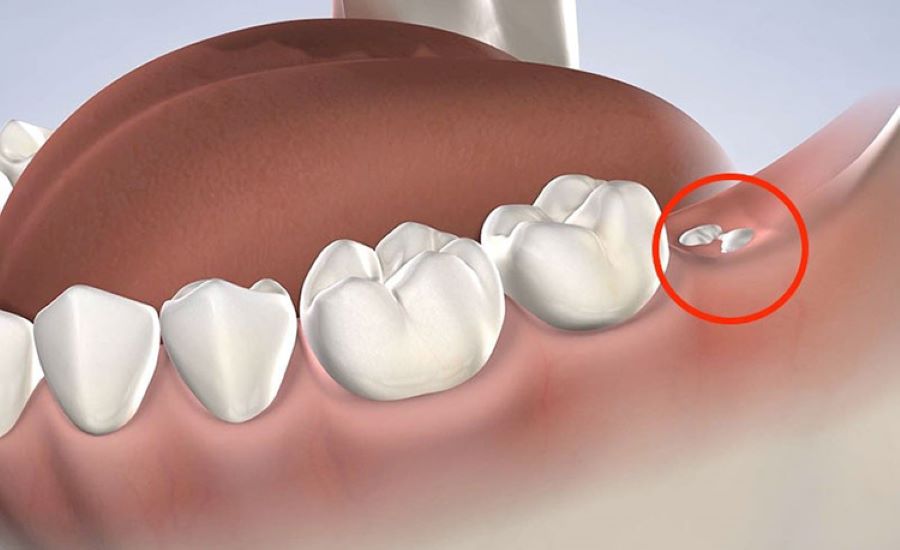

- Sau khi nhổ răng, bệnh nhân có thể kiểm tra số lượng chân răng được lấy ra. Từ đó so sánh với số chân răng thực tế của răng vừa nhổ.

- Số lượng chân răng ít hơn so với bình thường. Hoặc răng lấy ra không còn nguyên vẹn (bị gãy, mất phần gốc). Rất có thể bác sĩ đã vô tình bỏ sót một phần chân răng trong xương hàm.